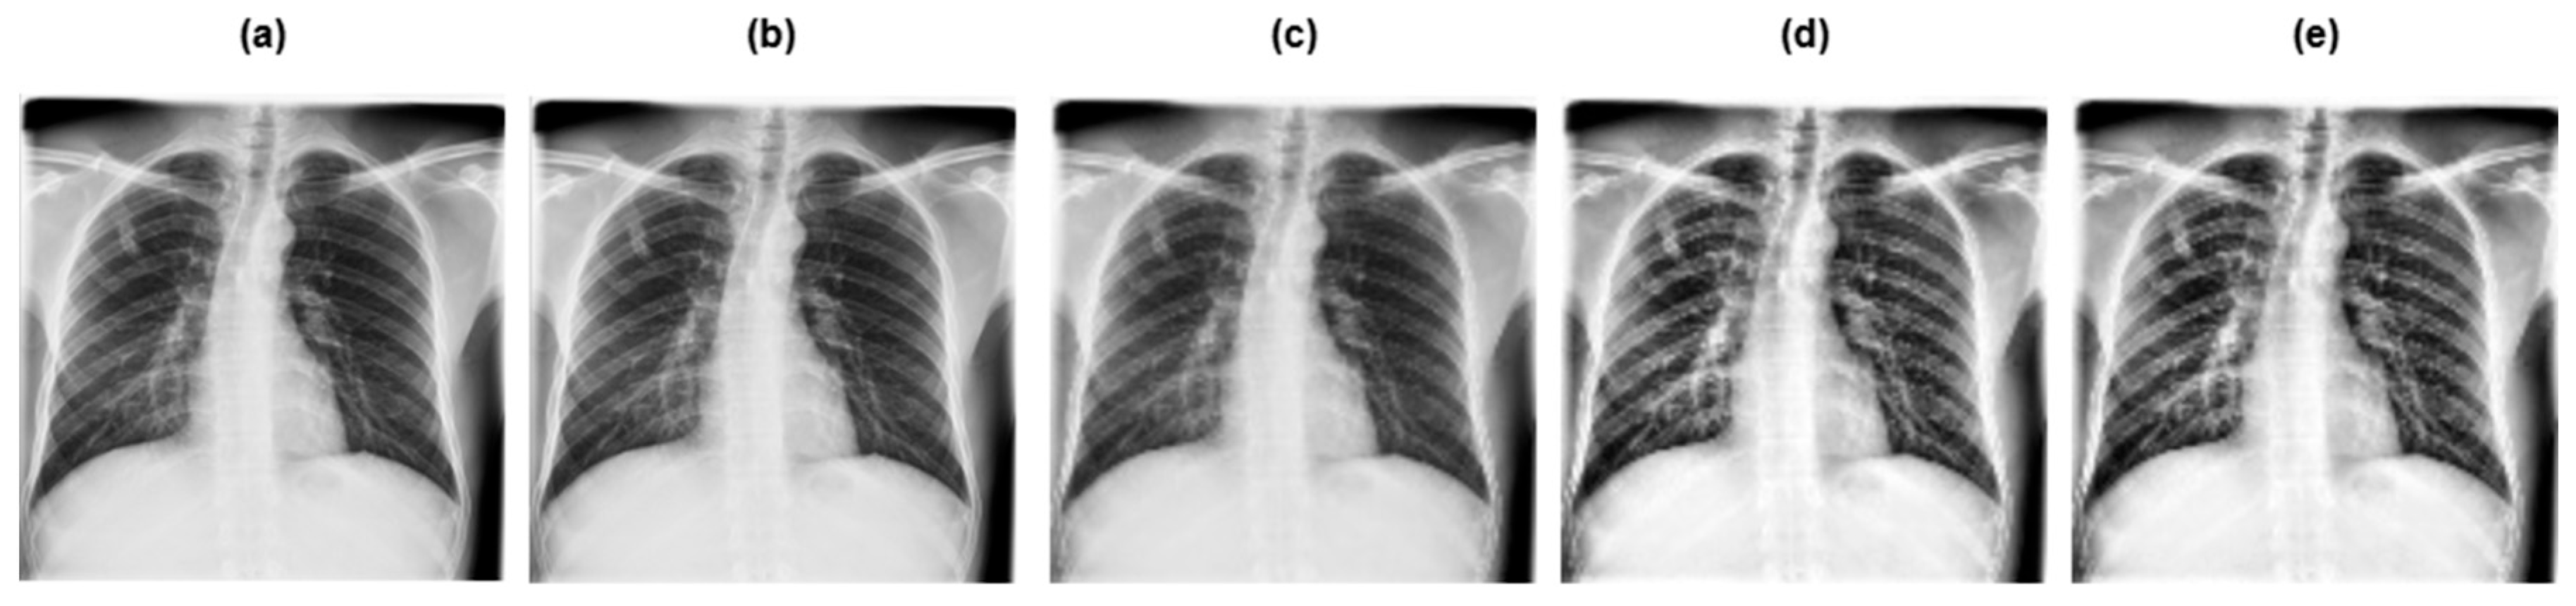

3.2. Data Preprocessing

- •

- Grayscaling: This refers to the conversion of RGB images to grayscale.

- Image resizing: The grayscale image was rescaled to a particular size, that is 128 × 128 pixels.

- Contrast Limited Adaptive Histogram Equalization (CLAHE): This improves the contrast of the image, making the tuberculosis area more pronounced and clearer.

- Image normalization: Normalization adapts the intensity range of individual pixels, typically to make the pixel values of an image more consistent and uniform to the human eye.

3.3. Data Augmentation